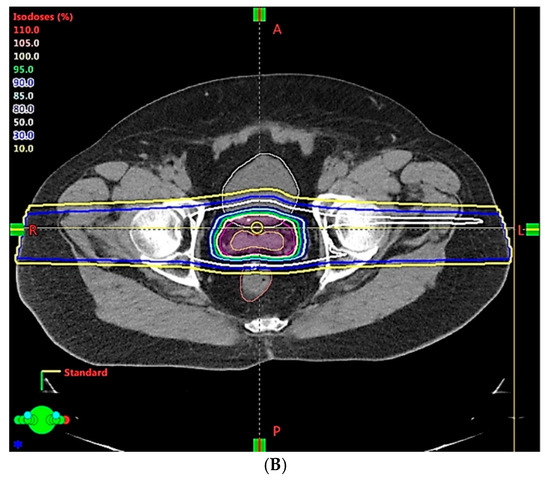

- Chung, H.; Polf, J.; Badiyan, S.; Biagioli, M.; Fernandez, D.; Latifi, K.; Wilder, R.; Mehta, M.; Chuong, M. Rectal dose to prostate cancer patients treated with proton therapy with or without rectal spacer. J. Appl. Clin. Med. Phys. 2016, 18, 32–39. [Google Scholar] [CrossRef]

- Polamraju, P.; Bagley, A.F.; Williamson, T.; Zhu, X.R.; Frank, S.J. Hydrogel spacer reduces rectal dose during proton therapy for prostate cancer: A dosimetric analysis. Int. J. Part. Ther. 2019, 5, 23–31. [Google Scholar] [CrossRef] [PubMed]

- Dinh, T.-K.T.; Lee, H.J.; Macomber, M.W.; Apisarnthanarax, S.; Zeng, J.; Laramore, G.E.; Rengan, R.; Russell, K.J.; Chen, J.J.; Ellis, W.J.; et al. Rectal hydrogel spacer improves late gastrointestinal toxicity compared to rectal balloon immobilization after proton beam radiation therapy for localized prostate cancer: A retrospective observational study. Int. J. Radiat. Oncol. 2020, 108, 635–643. [Google Scholar] [CrossRef] [PubMed]